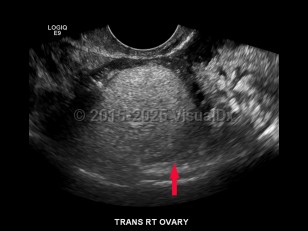

Ovarian cysts

Ovarian cysts are most commonly asymptomatic and diagnosed incidentally on physical exam or imaging. Sometimes the patient with an ovarian cyst may present with acute or chronic abdominal pain.